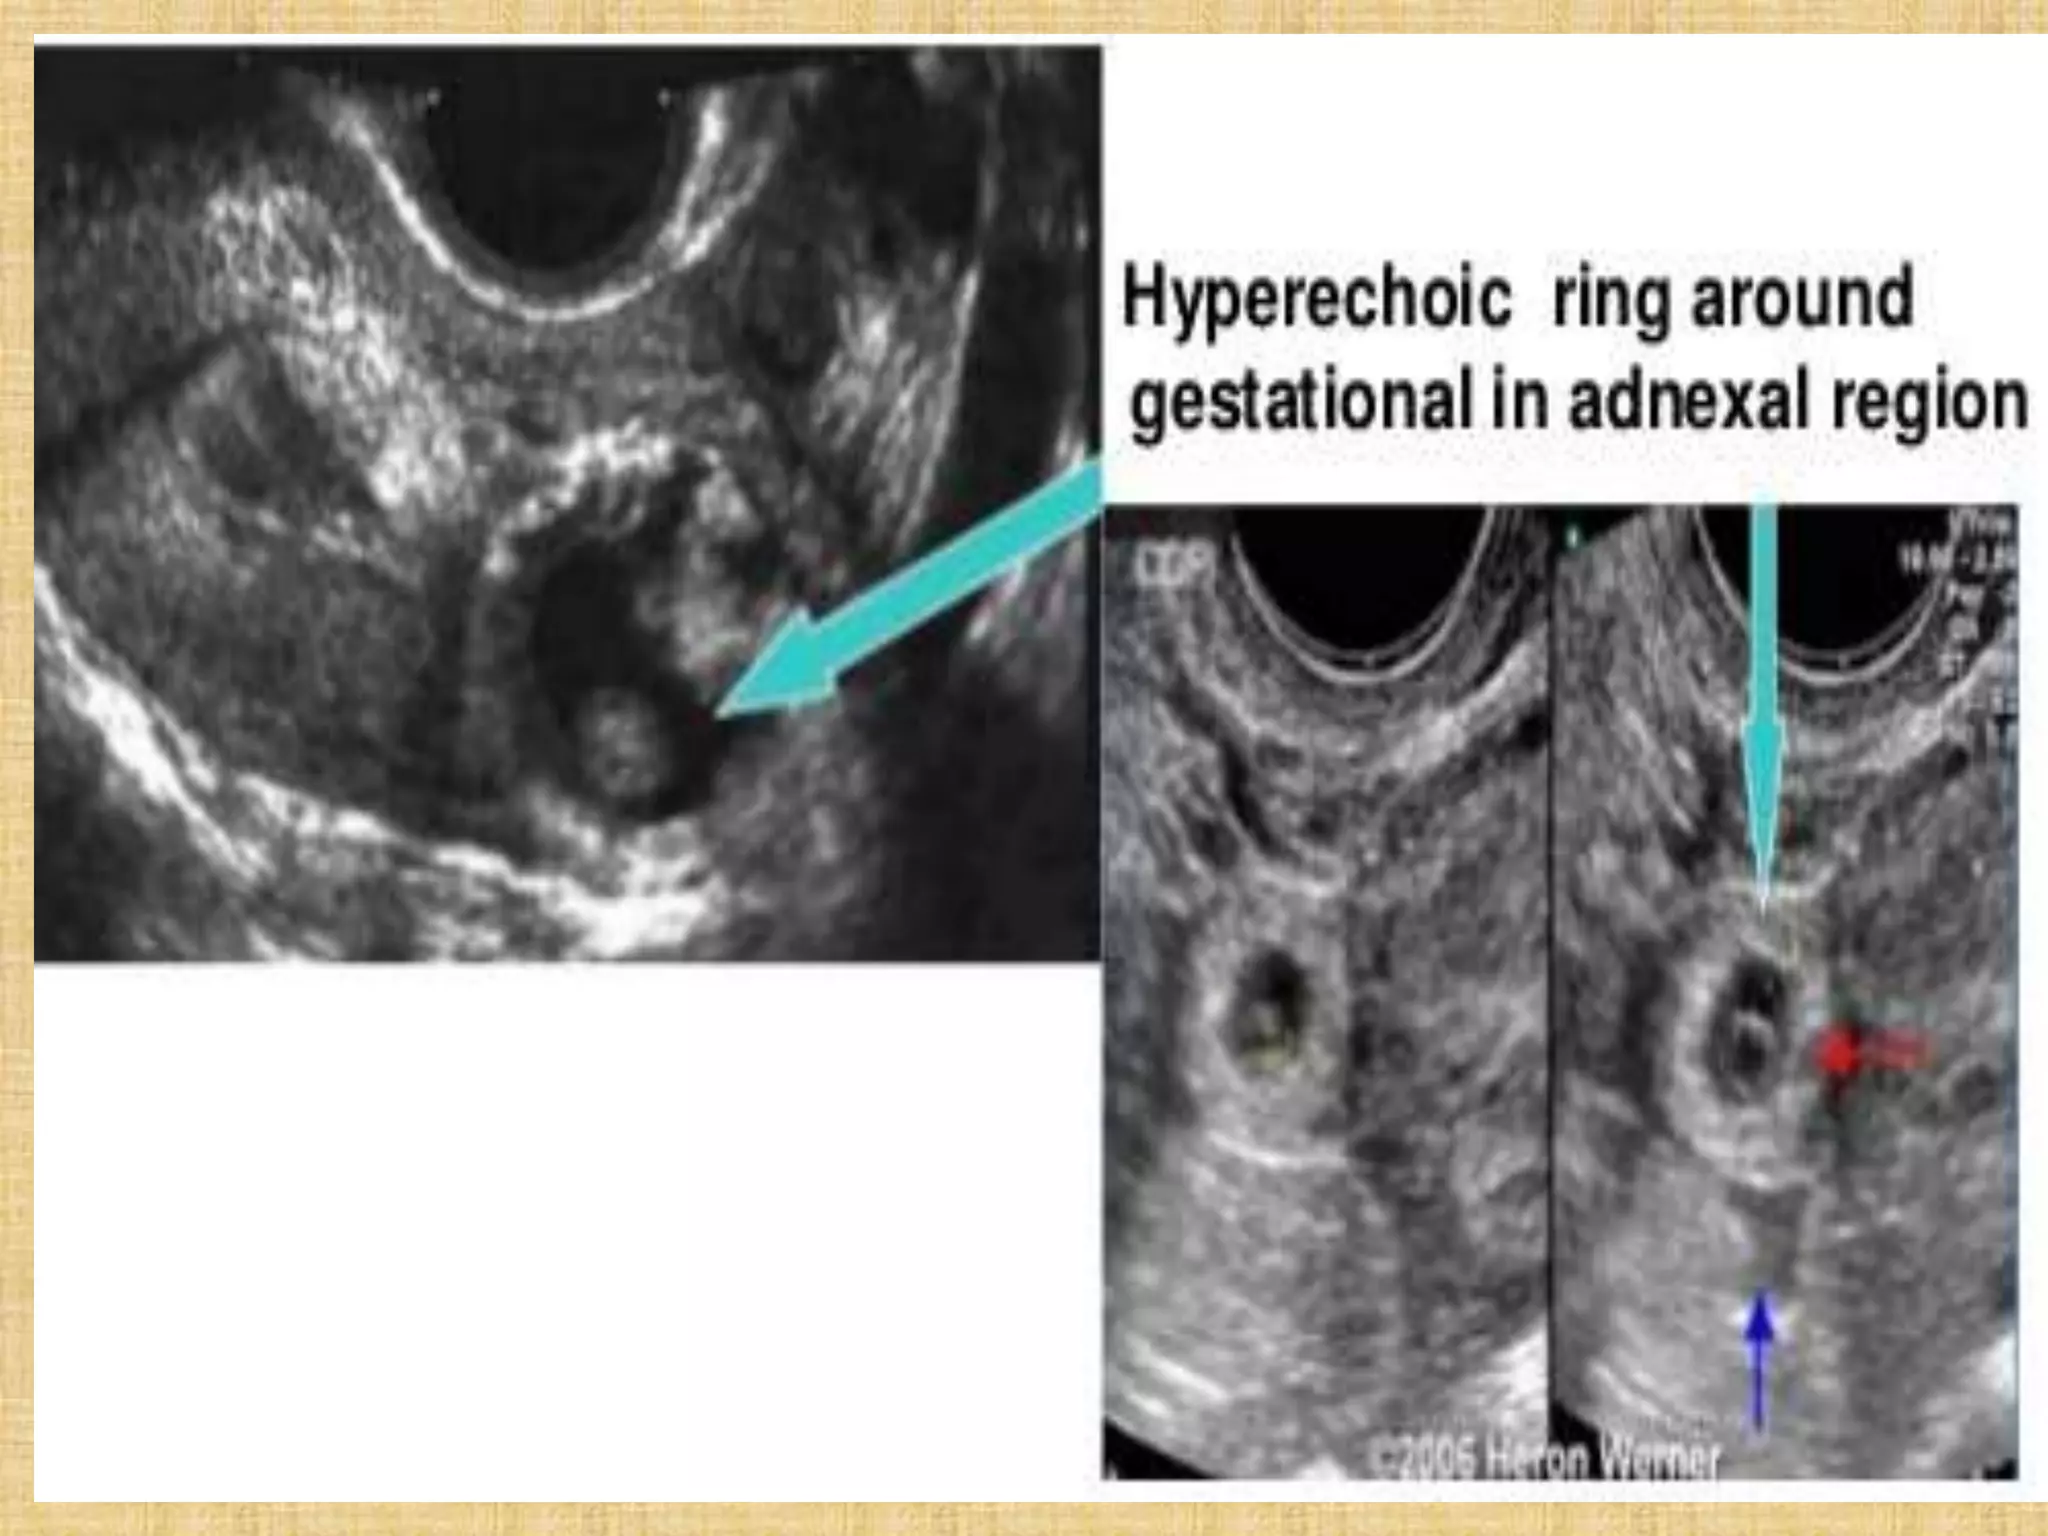

Tubal ring of ectopic pregnancy. (a) Transvaginal transverse view of the left adnexa shows

an echogenic ringlike mass (arrows) medial to the left ovary. Within the left ovary is a

thick-walled corpus luteum cyst (arrowheads). Note that the wall of the ectopic pregnancy

is more echogenic than the wall of the corpus luteum cyst. (b) Color Doppler image shows

more blood flow (arrowheads) to the corpus luteum than to the ectopic pregnancy (arrow).

Note that the “ring of fire” (hypervascular ring) appearance in the adnexa can be seen with

both ectopic pregnancy and corpus luteum.

Tubal ring ofectopic pregnancy. (a) Transvaginal transverse view of the left adnexa shows an echogenic ringlike mass (arrows) medial to the left ovary. Within the left ovary is a thick-walled corpus luteum cyst (arrowheads). Note that the wall of the ectopic pregnancy is more echogenic than the wall of the corpus luteum cyst. (b) Color Doppler image shows more blood flow (arrowheads) to the corpus luteum than to the ectopic pregnancy (arrow). Note that the “ring of fire” (hypervascular ring) appearance in the adnexa can be seen with both ectopic pregnancy and corpus luteum.